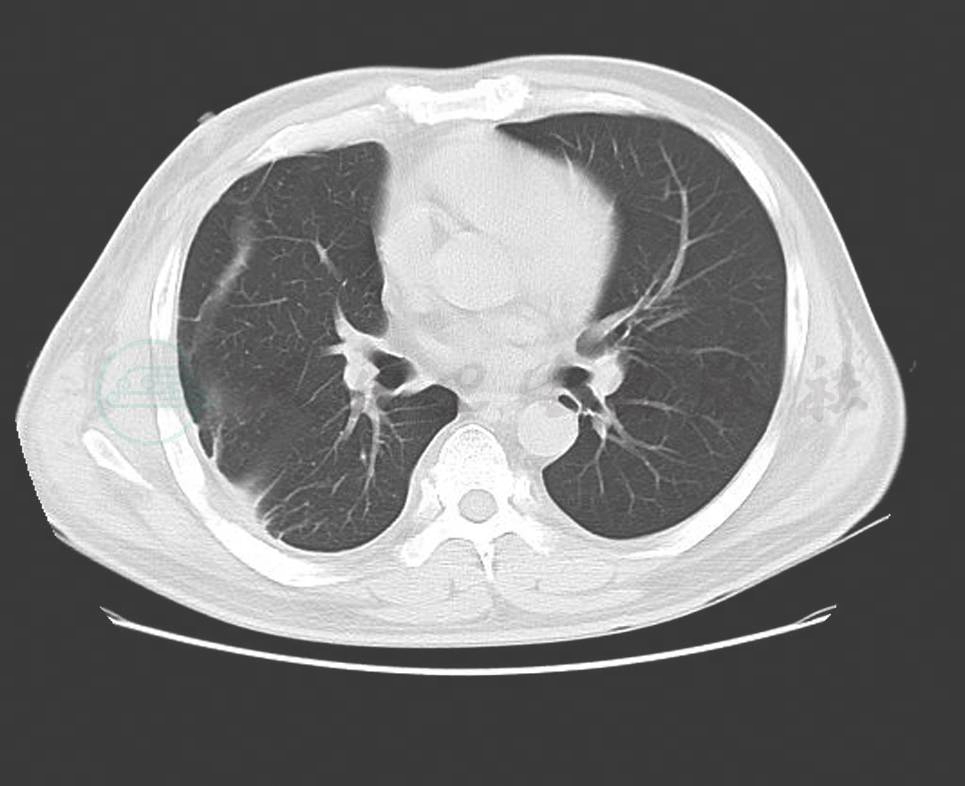

血象、血沉、结核三项、G试验、呼吸道病原及风湿免疫检查均未见异常。T-SPOT阳性。IgG 1410mg/dl,IgG4 355mg/dl。胸腔积液:送检胸水涂片及细胞病理学未见阳性结果;常规生化结果考虑为渗出液。胸部CT:右侧胸壁软组织占位并肋骨破坏及纵隔、腋窝淋巴结多发转移,不除外胸壁来源的恶性肿瘤;双肺炎症(图2、图3、图4)。小器官超声:双侧腋下多发肿大淋巴结。我院病理会诊(外院腋窝淋巴结标本):其内见血管内皮细胞增生显著。我院右侧腋窝淋巴结活检病理:Castleman病(巨大淋巴结增生症),透明血管型。免疫组化染色结果:CD3(T 细胞 +),CD20(B 细胞 +),CD21(+),CD34(血管 +),CD38(+),Ki-67(+25%~50%)。我院病理会诊(外院胸壁皮肤标本):考虑血管源性肿瘤,以上皮样血管内皮细胞瘤可能性大。我院右胸腹部皮肤活检:不除外血管肉瘤。北京协和医院病理会诊:(外院淋巴结):淋巴结结构存在,淋巴滤泡生发中心缩小,滤泡间见较多浆细胞浸润伴小血管增生。(外院皮肤):真皮胶原纤维及小血管显著增生,伴少许淋巴细胞浆细胞浸润;结合免疫组化考虑为IgG4相关性疾病,建议结合临床并作相关检查及测定血清IgG4水平。(我院淋巴结):CD138(+)、CD38(+)、IgG4/IgG(大于 40%)、IgG4(100 个 /HPF)。(我院皮肤):CD138(+)、CD38(+)、IgG45、IgG4(100 个 /HPF)。诊断考虑:淋巴结:Castleman disease。皮肤:不除外高分化血管肉瘤。

图4 治疗前(淋巴结)